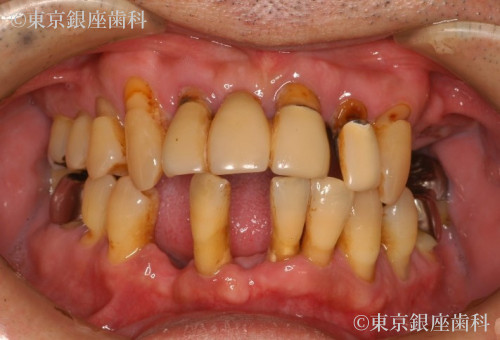

2型糖尿病の治療を経て歯周病の進行によって失われた咬合機能をワンデイインプラントにより回復。ただし費用の都合により上顎のみ手術。患者の希望により残存歯の多い下顎は義歯を使用した例。

Before

疾患 歯周病

義歯を使用しているが歯の動揺が激しく歯周病の進行が心配。

20代の頃からブラッシング時の出血等の症状があるも特に痛みもないため治療せず放置。

40代になると喫煙、糖尿病の影響も大きく歯周病が急激に悪化。

抜歯により義歯の装着を免れなくなった。

特に上顎の歯周病が進行していて歯の動揺、歯肉の腫れ、出血、咬合痛あり。歯石が帯状に付着しており磨き残しも多い。